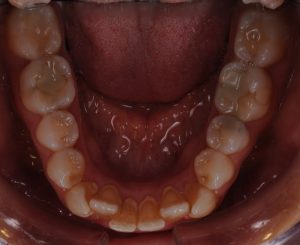

Maloclusión

Se caracteriza por una alineación incorrecta de los dientes, donde los dientes superiores e inferiores están en una relación normal, pero hay una falta de espacio que provoca que los dientes se solapen o estén apiñados.

Este problema puede generar dificultad para mantener una correcta higiene dental y afectar la estética de la sonrisa